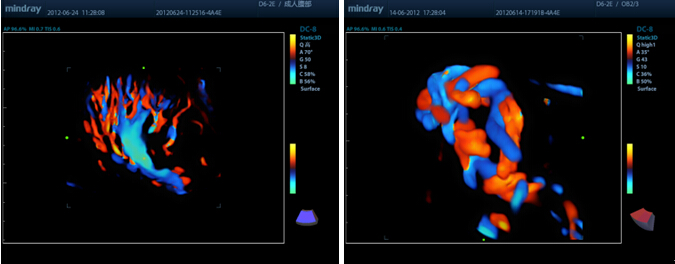

3D en color

Analice los vasos ramificados con eficacia gracias al Doppler 3D en color (disponible en 3D est├Ītico, solo con D6-2E).